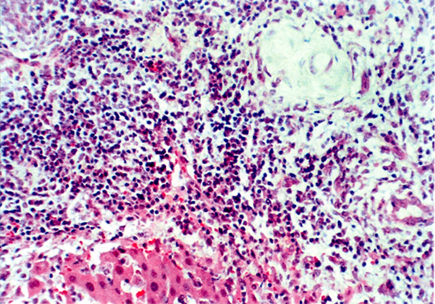

我们实验室以DA大鼠为供体,BN大鼠为受体进行原位肝移植,术后1~30天连续皮下注射环孢素A(lmg/kg/d),成功建立了大鼠肝移植慢性排斥反应模型。慢性排斥反应在术后30到60天内产生,中位生存期为58±14.93天。术后两个月病理学检查提示,移植物中有明显的淋巴细胞、中性粒细胞与嗜酸性粒细胞等炎性细胞浸润,同时胆管增生与胆道损伤情况也比较明显,胆管上皮局灶性坏死超过50%,一些胆管完全消失或纤维化。肝结构从肝小叶结构变化为大部分由结节与纤维组成的组织结构。残余肝细胞表现为退行性病变与坏死,连接汇管区出现完全与不完全纤维隔板。动脉管壁可见不同程度的纤维细胞与炎性细胞沉积,血管闭塞范围超过50%,一些动脉被完全阻断或纤维化(图4-2)。

图4-2 B

图4-2 A:DA-BN大鼠肝移植(皮下注射环孢素A lmg/kg/d×30天)术后60天,图示泡沫细胞阻塞性动脉病变,胆管明显减少甚至消失。B:DA-BN大鼠肝移植(皮下注射环孢素A lmg/kg/d×30天)术后60天,图示肝正常结构大量破坏,代之一纤维化组织和炎症,胆管减少,右上角显示正在纤维化消失的胆管(H&E染色,×100)